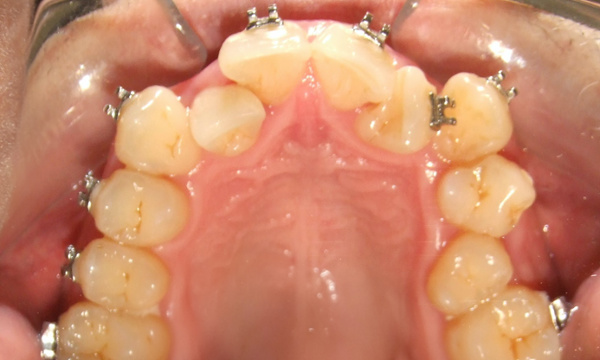

Not all orthodontic journeys start on the right path. This patient came to us with partial braces and a desire for clinical excellence. Dr. Martinez accepted the challenge, providing the expert, hands-on care necessary to "rescue" this complex case. After 24 months of specialized treatment in our Miami orthodontic practice, we achieved a healthy, stable, and properly aligned smile. Experience the difference 35 years of expertise makes.